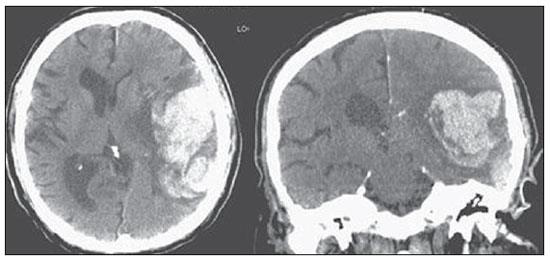

Analise a tomografia abaixo e indique qual o achado: